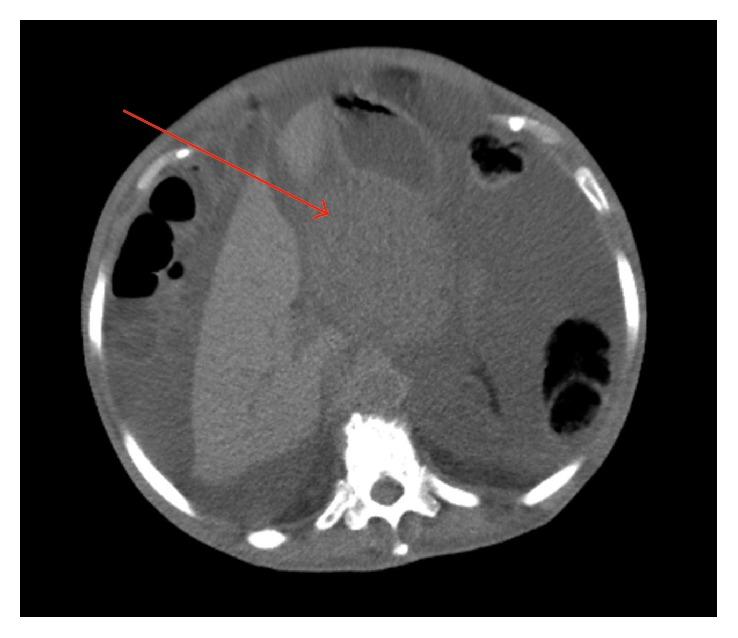

Pseudomyxoma peritonei (PMP) and extragastrointestinal stromal tumors (E-GISTs) are both rare entities. Most of the time, PMP is associated with an appendiceal tumor. An ovarian mucinous tumor can mimic appendiceal metastases. E-GIST is a mesenchymal tumor that can arise from the omentum, retroperitoneum, mesentery, or pleura. We present a case of an 87-year-old woman with mucinous carcinomatosis and acute intestinal occlusion submitted to an emergency laparotomy. She has found to have a borderline mucinous tumor of the ovary from the intestinal type with several lesions of pseudomyxoma peritonei and an E-GIST from the epiploons retrocavity (intermediated risk). In the literature, no relation was found between these two rare tumors. E-GIST was an incidental finding in the context of a mucinous carcinomatosis.

腹膜假黏液瘤(PMP)和胃肠道外间质瘤(E-GIST)均为罕见病症。大多数情况下,PMP与阑尾肿瘤相关。卵巢黏液性肿瘤可酷似阑尾转移瘤。E-GIST是一种间叶性肿瘤,可起源于大网膜、腹膜后、肠系膜或胸膜。我们报告一例87岁女性患者,因黏液性癌病和急性肠梗阻接受急诊剖腹手术。术中发现她患有肠型卵巢交界性黏液性肿瘤,伴有多处腹膜假黏液瘤病变,以及来自网膜后腔的E-GIST(中度风险)。在文献中,未发现这两种罕见肿瘤之间存在关联。E-GIST是在黏液性癌病背景下偶然发现的。